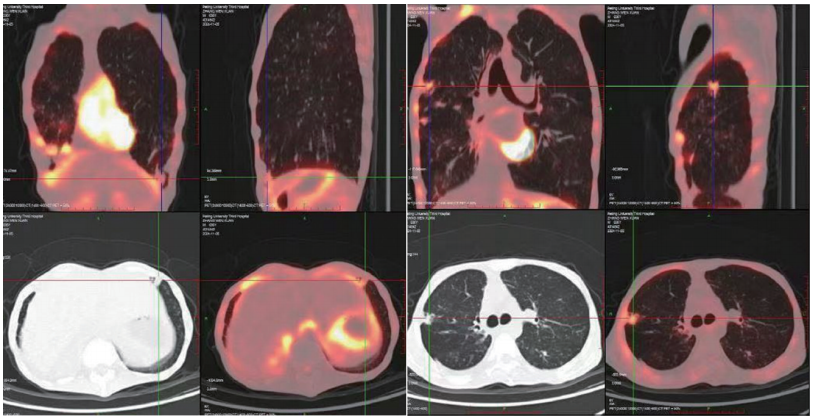

PET-CT 胸腺瘤术后,右侧胸膜多发增厚伴代谢增高,右肺门叶间胸膜处代谢增高结节,考虑转移,扫及全身多发肌肉代谢不同程度增高,考虑重症肌无力所致肌肉代偿性摄取可能(见图5) 。

图5 PCT-CT影像